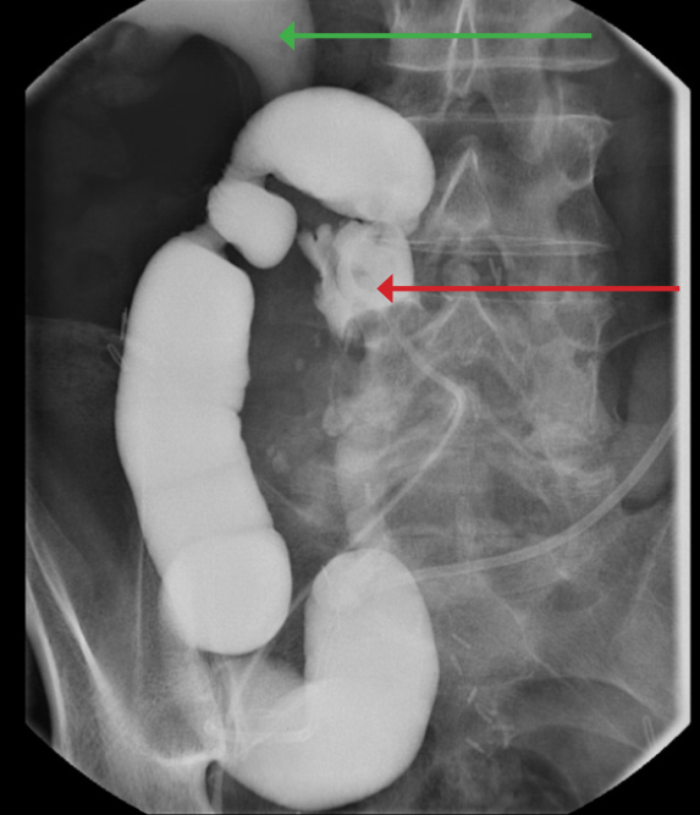

A 78-year-old male was transferred from a referring hospital. He had a cystectomy and ileal conduit performed 15 years previously and had recently been admitted with a clinical diagnosis of an infected obstructed kidney. The referring hospital had sited bilateral antegrade ureteric stents and were unable to remove the stent on the left side when the sepsis had settled. He had a long tortuous ileal conduit which was difficult to endoscope. A safety guidewire was placed retrogradely into the left kidney and after considerable manipulation, the stent was removed but the wire displaced and could not be replaced. Interestingly, some of the strings were still attached to the proximal end of the stent which may have led to difficulty with extraction. A perioperative loopogram demonstrated free reflux up both sides and the patient made an uncomplicated recovery, stent free.

Figure 1: Perioperative loopogram. Red arrow - Foley catheter in long tortuous conduit. Green Arrow - reflux into right upper tract.